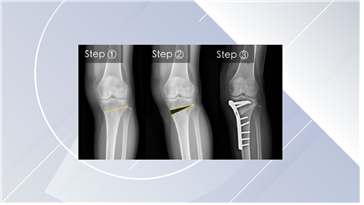

다리 모양이 O자로 변할 경우에는 치료가 가능한지, 가능하다면 어떻게 치료해야 하는건지 궁금합니다.

무릎 관절의 내측부위만 퇴행성 관절염이 와서 다리가 휜 경우에는 휜다리 교정술을 시행해 볼 수 있습니다. 교정술을 시행하게 되면 휜 다리가 펴지면서 하중을 외측으로 옮겨주어 내측부위의 관절염 진행을 늦출 수 있습니다. 휜다리 교정술은 뼈를 교정하는 절골술이기 때문에 교정된 뼈가 치유되는 충분한 기간이 필요합니다. 수술 후 엑스레이 검사를 주기적으로 촬영하여야 하고 6~8주 후에 수술한 다리로 걸을 수 있습니다. 뼈가 회복되는 기간은 3개월 정도의 시간이 필요합니다.